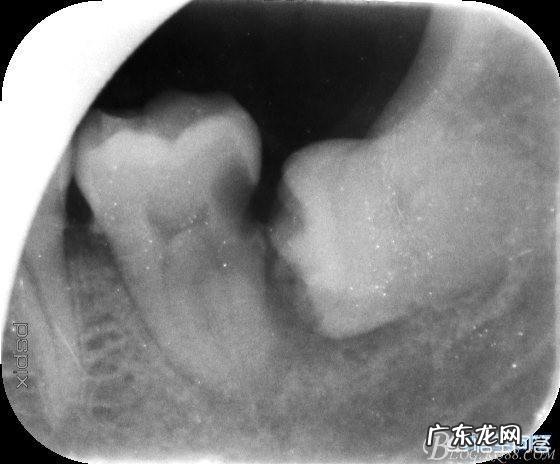

我右下角那颗智齿整整疼了两个月,去老家有名的私人牙科诊所看诊后,牙医给我两建议,抽牙神经或整颗牙拔掉 。抽掉牙神经起初是感觉不到牙疼,但是时间久了,整颗牙齿都会坏掉,这个方法zhi标不zhi本 。对于拔牙我又觉得比较恐怖难以接受,最后就配了些zhi牙疼的药回去了 。就这样又过了段时间,我明显感觉这种麻药对我已无效,渐渐这种痛感从牙齿波及到整个脑子,晚上睡着都能疼醒 。最终我决定去市里私人诊所拔牙 。那里的医生跟我说我的牙齿拔起来要比其他人费劲些,所以收费也高 。因为我的是水平阻生智齿,正常生长的牙齿都是竖着的,而我的是水平横向生长的 。长痛不如短痛,我还是让医生把它拔了 。记忆犹新的是,整整半小时的拔牙过程中,医生安慰我说:“我虽然不是这个医院最资深的医生,但绝对是我们这拔牙最温柔的”然后,然后这句话说完没多久,他就让助理护士去取铁锤去了 。我心里一万只动物奔过!!敲敲打打锤锤总算是解决了这颗牙齿!